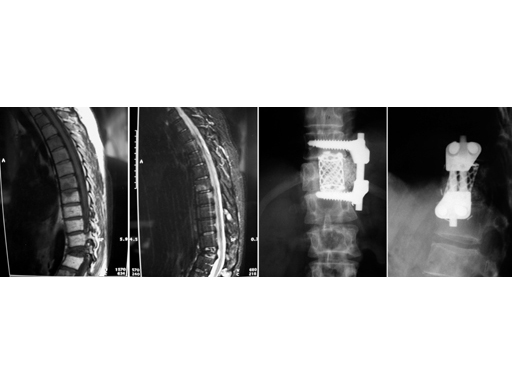

39-year-old woman, pathological fracture in L1 due to metastasis of breast cancer. Synmesh combined with Ventrofix.